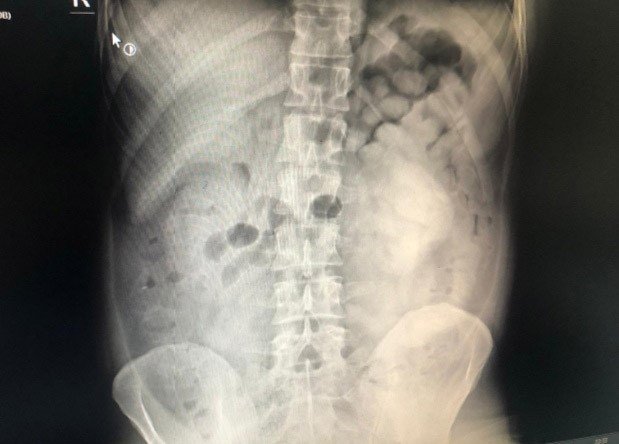

Doktor muayenesi ve çekilen film sonucunda şüphelinin sindirim sisteminde 800 gram eroin maddesi ele tespit edildi.